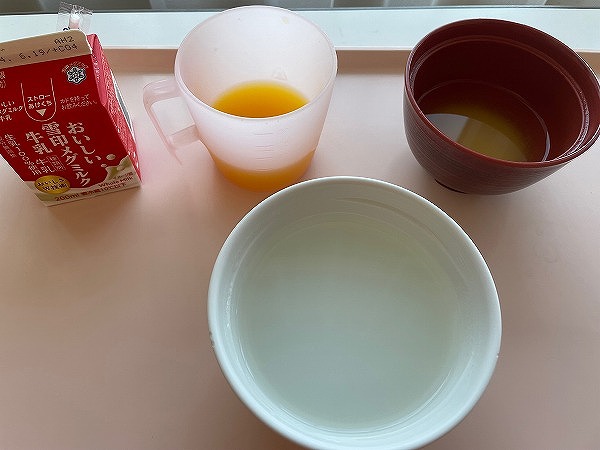

一日3食のメニューはすべて撮った。1日、1800カロリー。値段は一食100円なり。それでこのボリュームはうれしい。米は発芽米に変えてもらった。家でのご飯と同じにしてもらった。

11日から献立は「重湯」になった。米粒ひとつ入っていない。何も味がせず、何を食べているかもわからない。

この日の夕食も重湯。体内の物を出来るだけきれいに出すために昨日から下剤や浣腸を使い、胃や腸から入っている物を絞り出しているのだ。